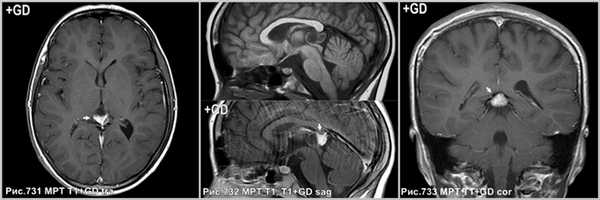

На КТ и МРТ солидные компоненты интенсивно накапливают контраст [34,43,49,53,130].

Интенсивное контрастирование солидных участков пинеоцитомы (стрелки на рис.731-733).

Постконтрастное Т1 демонстрирует накопление агента в солидном участке опухоли (стрелки на рис.734). В центре герминомы определяется петрификат (стрелка на рис.735) и отсутствующее обызвествление по периферии. Накопление контраста в стенке кисты шишковидной железы (головка стрелки на рис.736).